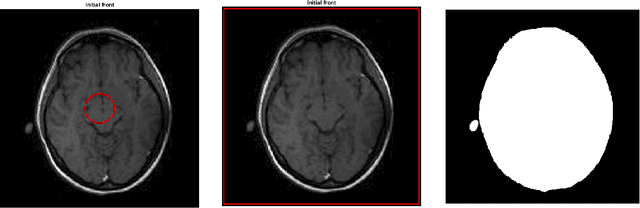

Abstract:The method is based on an adaptive "filtered" scheme recently introduced by the authors. The main feature of the scheme is the possibility to stabilize an a priori unstable high-order scheme via a filter function which allows to combine a high-order scheme in the regularity regions and a monotone scheme elsewhere, in presence of singularities. The filtered scheme considered in this paper uses the local Lax-Friedrichs scheme as monotone scheme and the Lax-Wendroff scheme as high-order scheme but other couplings are possible. Moreover, we introduce also a modified velocity function for the level-set model used in segmentation, this velocity allows to obtain more accurate results with respect to other velocities proposed in the literature. Some numerical tests on synthetic and real images confirm the accuracy of the proposed method and the advantages given by the new velocity.